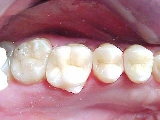

ANTES DEPOIS

O caso acima ilustra uma substituição de restauração de amálgama por um INLAY Artglass ( 1º molar) e restauração em resina composta no 2º molar.